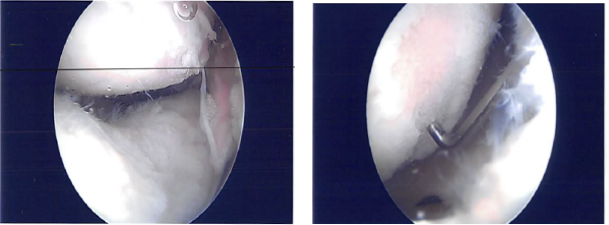

General anesthesia was induced on the patient, low thigh tourniquet was applied on the left thigh. A separate draping and dressing debris were performed and a lot of debris was found in the knee joint. There was patellofemoral arthritis.

There was fraying of the inner edge of the medial meniscus. There was OA grade 1 to grade 2 damage on the femoral condyle. The meniscus was debrided to a stable margin. A chondroplasty was performed in the medial femoral condyle.

The scope was entered to the intercondylar notch and entered in the lateral femoral condyle and found fraying of the inner margin of the lateral meniscus along with the small tear. Partial meniscectomy of the inner edge was performed.

Attention was focused on the patellofemoral joint where there was osteochondral damage, grade 1 to grade 2 on the medial articular surface of the patella. It was debrided to a stable margin. There was a large osteochondral damage, grade 2 to grade 3 over the trochlea, which also debrided. Final pictures were taken.